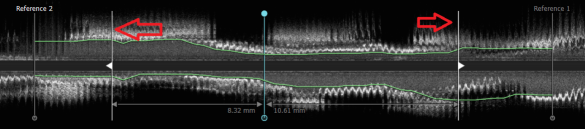

The IVUS dataset (IRB: 2021-05-002B) was collected from three independent hospitals, Taipei Veterans General Hospital (TVGH), Taichung Veterans General Hospital (VGHTC), and Kaohsiung Veterans General Hospital (VGHKS), Taiwan. A total of 151 individuals that undergo PCI and IVUS were included in the study. An IVUS mechanical system (OptiCross HD, 60 MHz Coronary Imaging Catheters, Boston Scientific Corporation) equipped with a 60 MHz wideband transducer collects raw data in DICOM format. Two physicians blinded to the participant information annotated approximately 87,505 frames of 2-dimensional images from 151 individuals. A cardiovascular is annotated within the target length indicated by the white line in the longitudinal view, which is the narrowing range of the lumen area owing to plaque growth as shown in Figure 5. Each adjacent frame is approximately 3 mm apart. There are a certain number of frames depending on the length of the cardiovascular system. There are two classes in total, and each frame is annotated at the pixel level; class ”0” for the non-region-of-interest area and class ”1” for the region-of-interest area, which include the EEM, lumen, or plaque burden areas.

Refer to caption

Figure 5: Cardiovascular appearance in the longitudinal view.